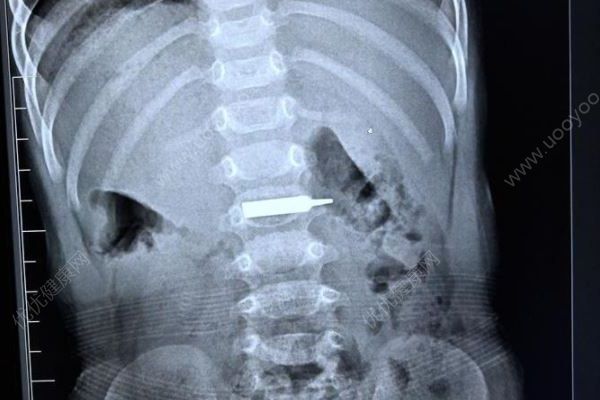

13日22时左右,一名16个月大的男孩因为吞了螺丝刀的刀头,被家人紧急送到长春市儿童医院救治,经过近两个小时手术,医生将异物安全取出。儿科医生提醒:宝宝吞入消化道的异物最常见为别针、缝针、发夹、钱币、纽扣、圆钉、螺丝钉、小玩具等。家长们如果发现宝宝口含某物玩弄,一定要让宝宝吐出,不要留下隐患。如果已经出现误食情况,且异物还未到胃中,家长可尝试拍背,帮助孩子吐出异物,一旦误服异物,没有办法排出,一定及时就医!

22时左右,鹏鹏来到儿童医院,门诊大夫一边通知医院行政总值,一边开启绿色通道为孩子进行检查,确认异物位置。行政总值通知内镜科全科医生赶回医院准备手术。

“接到电话就往回赶,孩子的情况十分危急,异物很尖锐,如果不及时取出,进入肠道,必定造成穿孔,到那时外科手术就避免不了了。”医院内镜科副主任边鹏介绍,23:30时,科内所有医护人员全部就位,鹏鹏被推进手术室,进行无痛胃镜下消化道异物取出手术。

“太惊险了,手术前,这个螺丝刀头一半在胃里,一半已经进入十二指肠,晚一步后果不堪设想。”边鹏介绍,手术还是有很大难度,鹏鹏胃里当时都是食物残渣,手术第一步就是将异物拽回到胃里,这个过程中,异物直接就掉进食物残渣里。“我们先对孩子的胃进行清理,然后才将异物取出。”边鹏说。手术全程2个小时,很顺利,经过测量,发现异物长约3厘米左右,鹏鹏今天可以喝水了,也可以少量的进食些米汤,明后天就可以办理出院了。